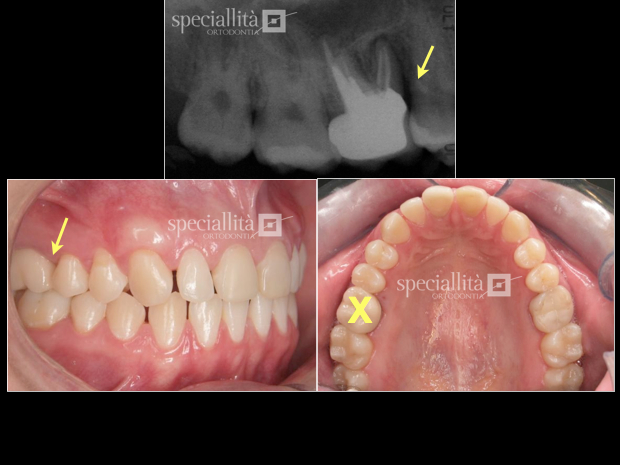

Perda óssea no 1o molar superior direito causada por prótese unitária invadindo espaço biológico. Planejamento envolvendo a exodontia do 1o molar e fechamento do espaço por  mesialização do 2o e 3o molares

Sequência de movimentação do 2o e 3o molar para mesial

Vista oclusal do  fechamento completo do espaço da extração realizada